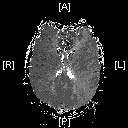

fig. 4: AFTER the procedure: a perfusion MRI showing the normalization of flow to the left middle cerebral artery territory.

A second perfusion MRI was completed after treatment and showed normalization of flow to the effected area (fig. 4).